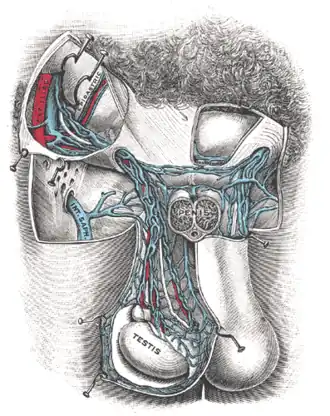

The pampiniform plexus (from Latin pampinus 'tendril' and forma 'form') is a venous plexus – a network of many small veins found in the human male spermatic cord, and the suspensory ligament of the ovary. In the male, it is formed by the union of multiple testicular veins from the back of the testis and tributaries from the epididymis.

The veins of the plexus ascend along the spermatic cord in front of the vas deferens. Below the superficial inguinal ring they unite to form three or four veins, which pass along the inguinal canal, and, entering the abdomen through the deep inguinal ring, coalesce to form two veins. These again unite to form a single vein, the testicular vein, which opens on the right side into the inferior vena cava, at an acute angle, and on the left side into the left renal vein, at a right angle. The pampiniform plexus forms the chief mass of the cord.

In addition to its function in venous return from the testes, the pampiniform plexus also plays a role in the temperature regulation of the testes. It acts as a countercurrent heat exchanger, cooling blood in adjacent arteries. An abnormal enlargement of the pampiniform plexus is a medical condition called varicocele.